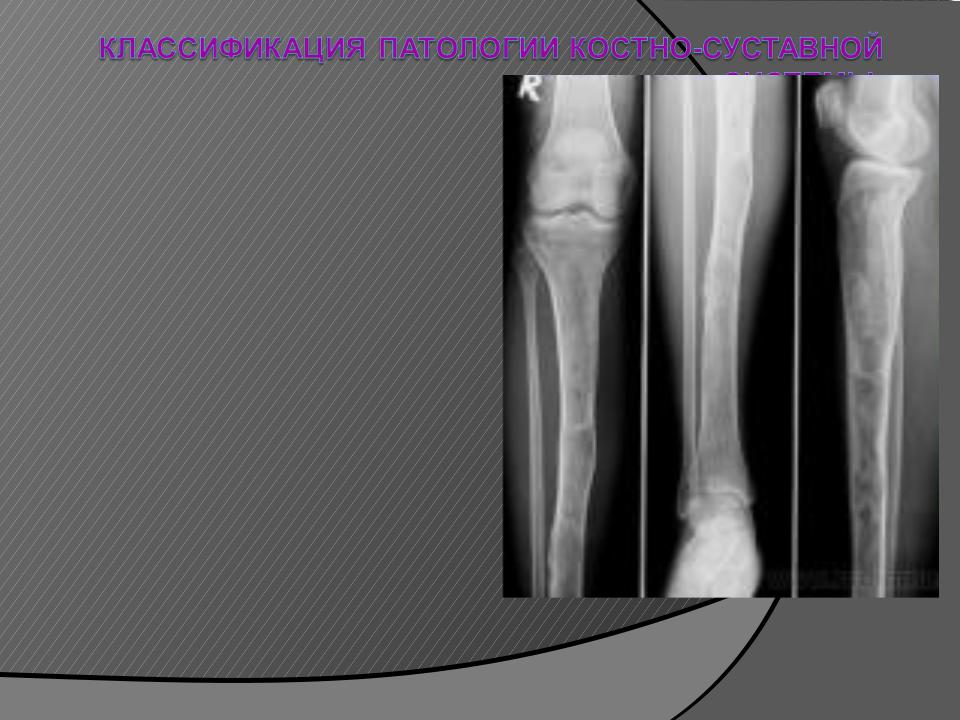

Рентгеновские снимки и визуализация болезни Педжета

Раздел: Мудрость в объективе